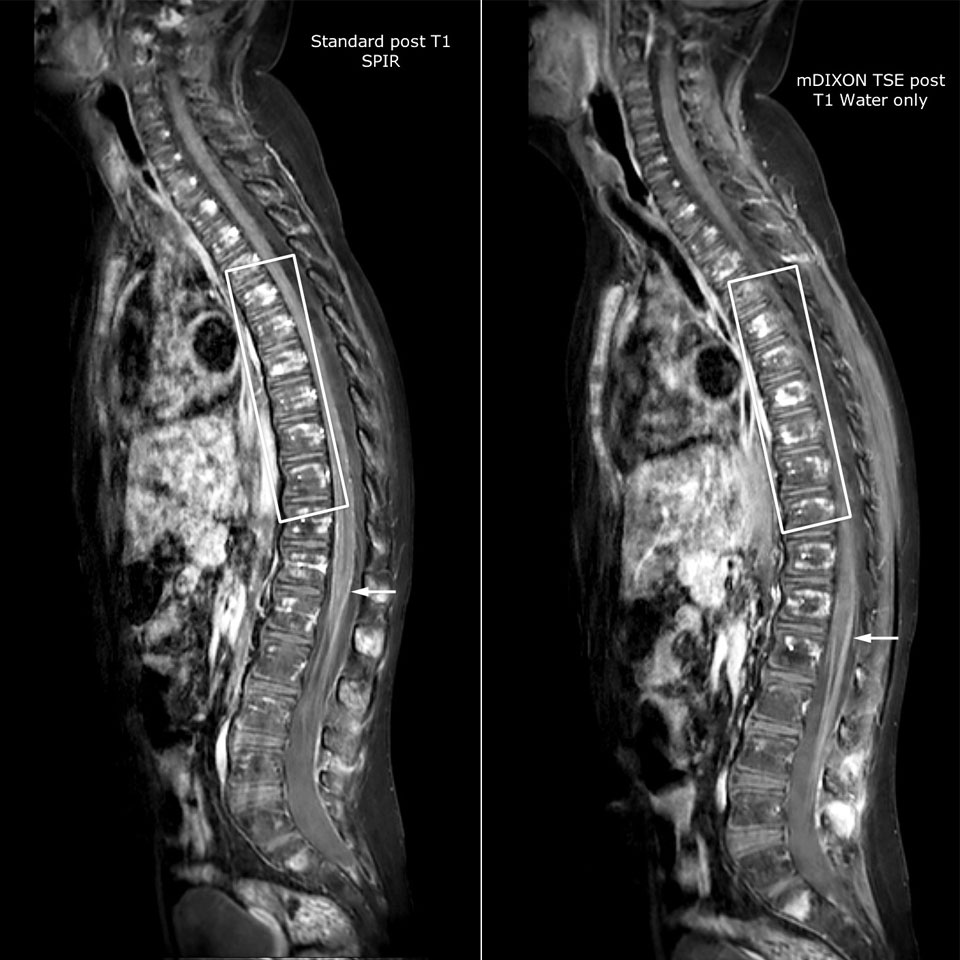

Philips mDIXON TSE is a two-point DIXON technique that separates water and fat signals, for time-efficient fat-free imaging, even in challenging neuro anatomy.

“mDIXON TSE has been one of the most significant improvements in imaging sequences that we have utilized to date at PCH,” says Dr. Miller. “Its multi-parametric acquisition allows us to obtain fat suppressed images and equivalent non-fat suppressed T2 images all in the same sequence. In addition, prior methods of fat suppression could be artifactually corrupted by poor patient anatomy or poor operator application, but with mDIXON we now have a robust and reliable method of fat suppression.”

Fat saturation is historically challenging at the ends of fields of view, especially in total spine imaging and in difficult patient anatomy such as the lower regions of the neck. “Due to the unique fat suppression capabilities of mDIXON, however, these challenges no long apply,” says Dr. Miller. “We routinely obtain homogeneous fat suppression under virtually all conditions. It has also led to some efficiencies by not having to repeat sequences because of that technical failure.”

mDIXON TSE makes a difference

“mDIXON TSE is most useful in patients with lesions or abnormalities in the soft tissues such as the face and neck, and for patients with contrast enhancing abnormalities that are mostly visible with fat suppression,” says Dr. Miller. “All our spine imaging now routinely contains mDIXON water-only T2 images, and this allows us to identify pathology that may be obscured by non-fat suppressed imaging such as injuries of the bone. And it’s not necessary to obtain additional standard TSE T2 images because the in-phase mDIXON images are equivalent to standard TSE T2 images.”

“mDIXON TSE has increased our diagnostic confidence in ruling in or ruling out abnormalities in which fat suppression is critical to diagnosis, such as metastatic disease or osseous abnormalities.”

Miller JH, Pokorney A, Naidu P, Eggers H, Shar M, Perkins T. Improved Fat Suppression and Field Homogeneity of mDixon TSE Total Spine Imaging compared to SPIR Fat Saturation for Post-Contrast T1-weighted Imaging. Proceedings of the Joint Annual Meeting of the ISMRM-ESMRB. Milan, Italy: International Society for Magnetic Resonance in Medicine, 2014.

“We routinely obtain homogeneous fat suppression under virtually all conditions.”